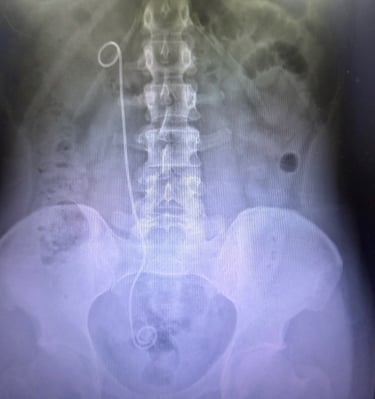

Galería

Imágenes que reflejan cuidado y confianza.